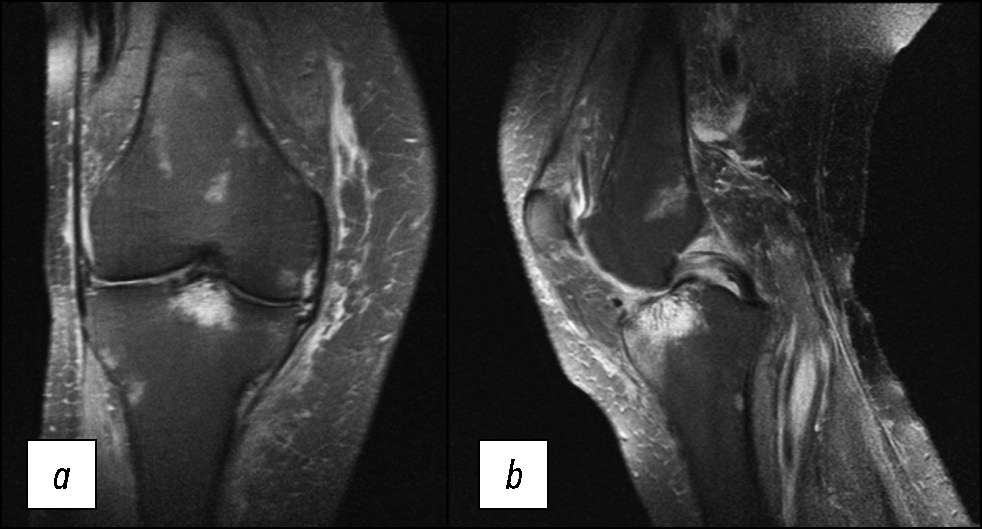

На выполненных рентгенограммах патологии не выявлено. Пациент наблюдался в клинике по месту жительства с диагнозом «остеоартрит коленного сустава». В связи с неэффективностью применения нестероидных противовоспалительных препаратов выполнил МРТ-исследование, на котором выявлен отёк костной ткани в области наружного мыщелка бедренной кости (рис. 1), плавно переходящий на внутренний мыщелок.

Рис. 1. МР-томограммы коленного сустава: а, b — изображение в T2w-STIR режиме, с — изображение в режиме Т1 в корональной проекции, и графическое изображение остеонекроза мыщелка в сагиттальной проекции (d).

Fig. 1. MR images of the knee: а, b — T2-weighted short-tau inversion recovery (T2w-STIR), с — T1-weighted sequences in the coronal projection and a graphic image of an osteonecrosis (d).

Состояние расценено как идиопатический асептический некроз наружного мыщелка бедренной кости I стадии по классификации ARCO (остеонекроз) (M87.0) [8].

Особенности отёка костной ткани: достаточно равномерный, без каких-либо линий и включений, распространяется на большую часть мыщелка. Гиалиновый хрящ не вовлечён в патологический процесс, имеет ровную поверхность без деформации, что характерно для начальной стадии асептического некроза [9].